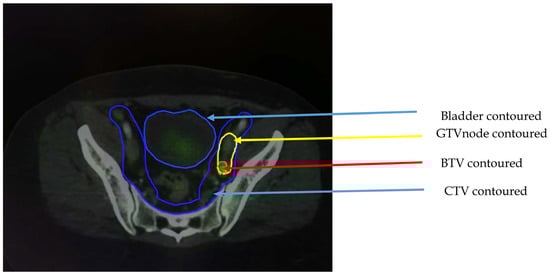

3.4.1. Cervical Cancer